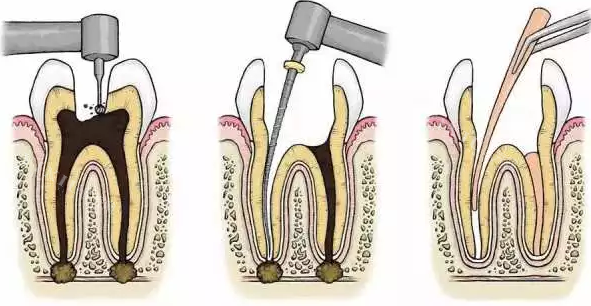

根管治疗:600元起